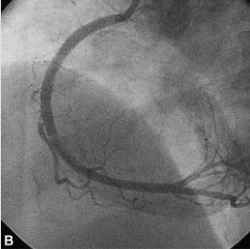

협심증, 심근경색을 진단하는 가장 정밀한 검사로 카테터라고 불리는 직경이 가는 플라스틱관(직경 2mm, 길이 약 1~2m)을 손목(요골동맥)이나 사타구니(대퇴동맥)를 통해 삽입하여 심장에 도달시킨 뒤 관상동맥 조영제를 주사하고, X-선을 이용하여 촬영하게 됩니다. 이를 통해 관상동맥의 비정상적인 구조나 폐색, 협착 부위를 확인하고, 약물치료나 경피적 관상동맥 중재술 또는 관상동맥우회술 등의 치료방향을 결정하게 됩니다.